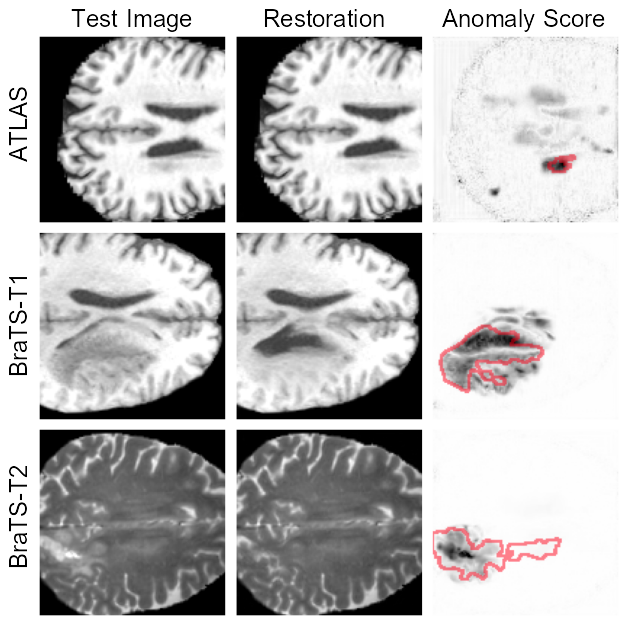

Performance analysis: To quantitatively evaluate our method, we use the most common metrics in the medical UAD literature: Average Precision (AP) and an estimate of the best possible Sørensen-Dice index ([Dice] score). Some qualitative results are reported in Fig. 3.

Refer to caption

Fig. 3: Restoration results on test images drawn from the ATLAS [17], BraTS-T1, and BraTS-T2 [18], after step_size=25𝑠𝑡𝑒𝑝_𝑠𝑖𝑧𝑒25step\_size=25italic_s italic_t italic_e italic_p _ italic_s italic_i italic_z italic_e = 25, along with anomaly scores AS𝐴𝑆ASitalic_A italic_S in grayscale compared with the ground truth outline in red.